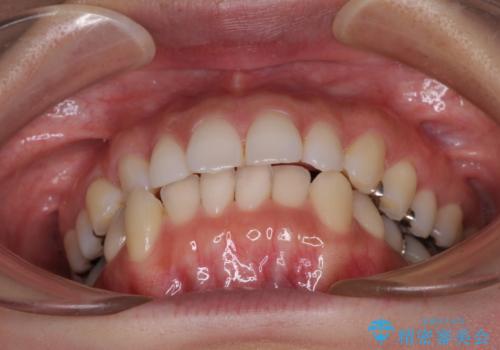

- 口元の突出感と口の閉じにくさを気にして来院された患者様です。

上下左右第一小臼歯4本を抜歯し、ワイヤー装置にて口元を引っ込めるよう矯正治療を行うこととしました。

奥歯が前方に傾斜していることで深く咬みこむ(ディープバイト)状態であったので、なかなか抜歯したスペースが閉じず、様々な方法でディープバイトを改善しながら治療を進めていくこととなりました。